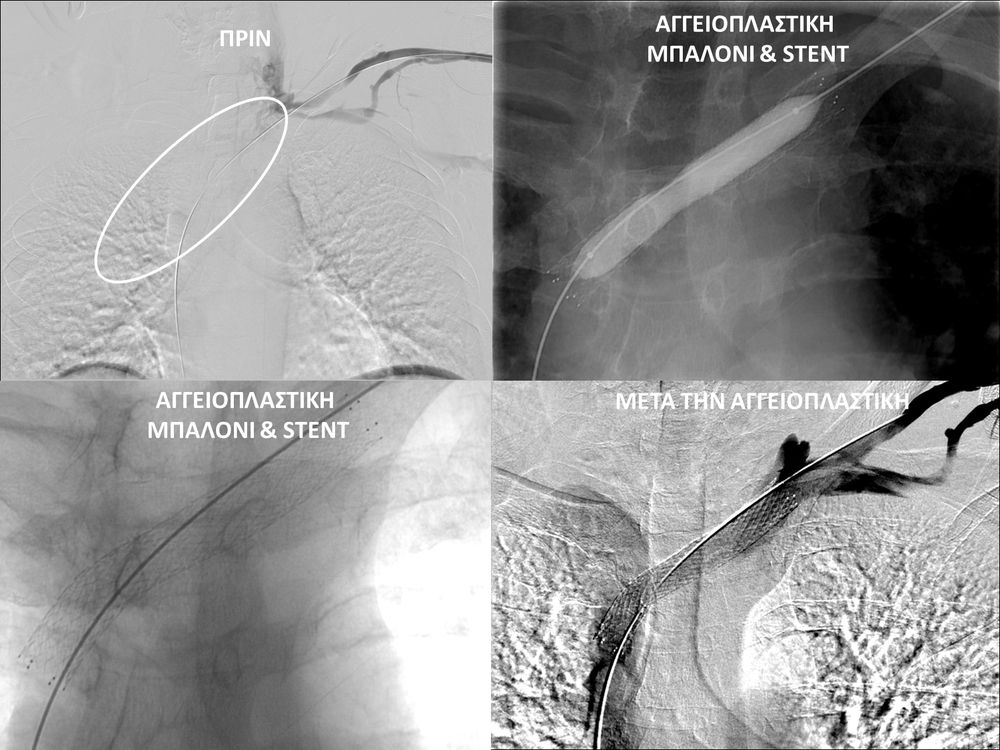

- Φιστουλογραφία ονομάζεται η αγγειογραφία των μοσχευμάτων-fistula αιμοκάθαρσης. Είναι είναι μια ελάχιστα επεμβατική διαγνωστική εξέταση που ενδείκνυται για την ανάδειξη στενώσεων που θέτουν σε κίνδυνο την λειτουργία της αγγειακής πρόσβασης και δεν επιτρέπουν την επαρκή αιμοκάθαρση. Η εξέταση διενεργείται με τη χρήση αγγειογράφου και ιωδιούχου σκιαγραφικού μέσου.

- Η φιστουλοπλαστική είναι μια ελάχιστα επεμβατική μέθοδος αντιμετώπισης της δυσλειτουργίας των αρτηριοφλεβικών προσβάσεων αιμοκάθαρσης (μοσχευμάτων ή fistula) λόγω αρτηριακών ή φλεβικών στενώσεων, χωρίς να χρειαστεί χειρουργείο. Η φιστουλοπλαστική διενεργείται σε αγγειογραφική σουίτα με συνθήκες αποστείρωσης και υπό τοπική αναισθησία, ενώ η θεραπεία περιλαμβάνει συνήθως την διαστολή της αγγειακής στένωσης με ειδικό «μπαλονάκι» υψηλών πιέσεων. Στη περιπτωση όπου οι αγγειακές διαστολές δεν επιφέρουν το επιθυμητό αποτέλεσμα, τοποθετούνται μεταλλικές ενδοπροθέσεις (stents).